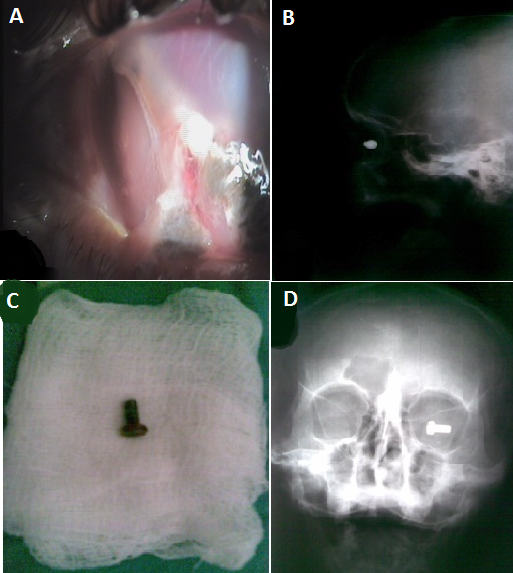

Patient âgé de 28 ans admis aux urgences ophtalmologiques pour baisse d'acuité majeure avec douleur oculaire suite à un traumatisme par projection oculaire d'un corps étranger. A l'examen, l'acuité visuelle est à perception lumineuse douteuse avec plaie de cornée, un segment antérieur remanié avec hernie de l'iris ( A), l'examen du segment postérieur est impossible. Une radiographie standard des orbites de face et de profil ont été demandées et ont objectivé un corps étranger radio opaque ayant la forme d'une vis au niveau de l'orbite droite (B et D). Le patient a bénéficié d'une extraction à l'éléctroaimant du corps étranger géant intraoculaire qui s'est révélé être une vis (C) avec suture de la plaie cornéenne. L'acuité visuelle du patient s'est limitée à une perception lumineuse positive.